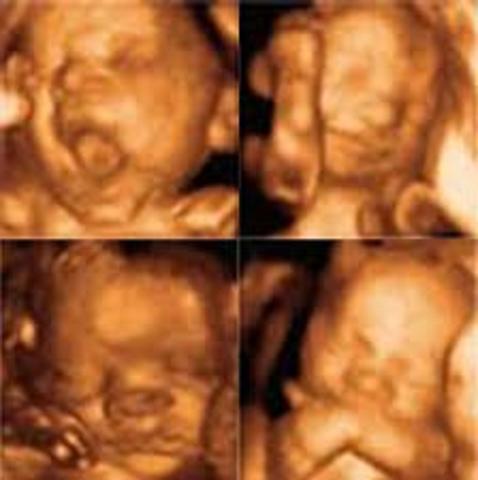

¡Hola mamá! Esta semana comienzas la recta final, de la semana 28 a la 42 es el tercer trimestre. Tu bebé sigue creciendo y su sistema nervioso central comienza a desarrollarse, algunos estudios señalan que el bebé a partir de la semana 28 empieza a comprender y es capaz de sentir todo lo que ocurre a tu alrededor.

El cerebro de tu bebé comienza a crecer y ser más pesado, su piel también va cambiando, empezará a tener grasa bajo la piel, lo que le va dando un aspecto redondeado. En estas semana